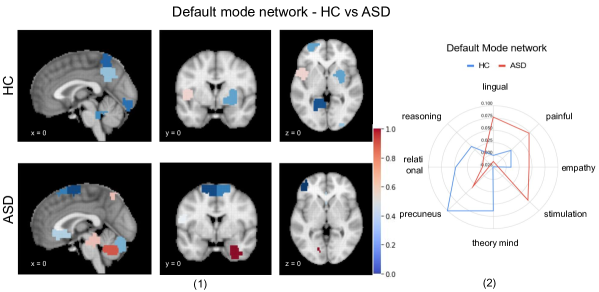

2. Ability of the prompt’s attention vector to differentiate between ASD and HC subjects: We investigate the first row of the learned attention matrix, namely the attention of ROIs corresponding to the prompt. The ROI-wise normalized attention scores shown in Fig. 2(4) are generated using averaged prompt vectors over correctly classified test data, where red to blue indicate attention scores from high to low (dark red:1 to dark blue: 0). As evident from the figure, clear differences can be seen in the important brain regions among ASD and HC subjects. Additionally, most differences in the prompt vector embeddings are seen in DMN and SMN (supporting figures in the appendix), consistent with previous neuroscience literature.

3. Meta-analysis of the important functional networks that influence ASD prediction: DMN and SMN networks have been found to be crucial for ASD prediction based on Fig. 2(4). Using the difference of the prompt vector values in those regions between ASD and HC subjects, Fig. 2(5) was generated based on Meta-analysis using Neurosynth222The meta-analytic framework (www.neurosynth.org) provides the posterior probability P𝑃P(Feature\midCoordinate) for psychological features (i.e., word or phrase) at a given spatial location based on neuroscience literature. database[27]. Regions in DMN were found to be associated with trait keywords such as empathy, painful, stimulation, orienting and spatial, whereas regions in the SMN showed higher correlations with eye movement, ventral premotor, somatosensory and speech production.